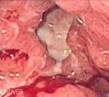

https://commons.wikimedia.org/wiki/File:Gastric_ulcer_3.jpg

Description English:

Endoscopic image of gastric ulcer, biopsy proven to be en:gastric cancer. Released into public domain on permission of

patient -- Samir धर्म 08:44, 7 June 2006 (UTC)

Modifed: A.G. DiGiovanna

Added labels and

lines.